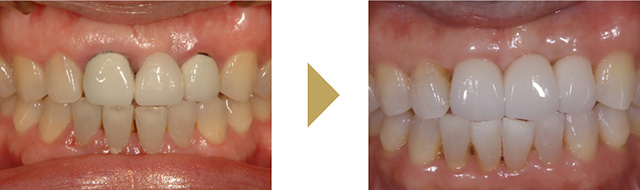

歯周外科治療

麻酔をして少し歯茎を開いてあげると、歯周病菌を目で見て除去することが可能になり、徹底的に歯周病菌を除去できます。また格段に歯周病治療の成績が向上します。条件が揃えば、失ってしまった骨を増やすような再生治療を行うことも可能です。